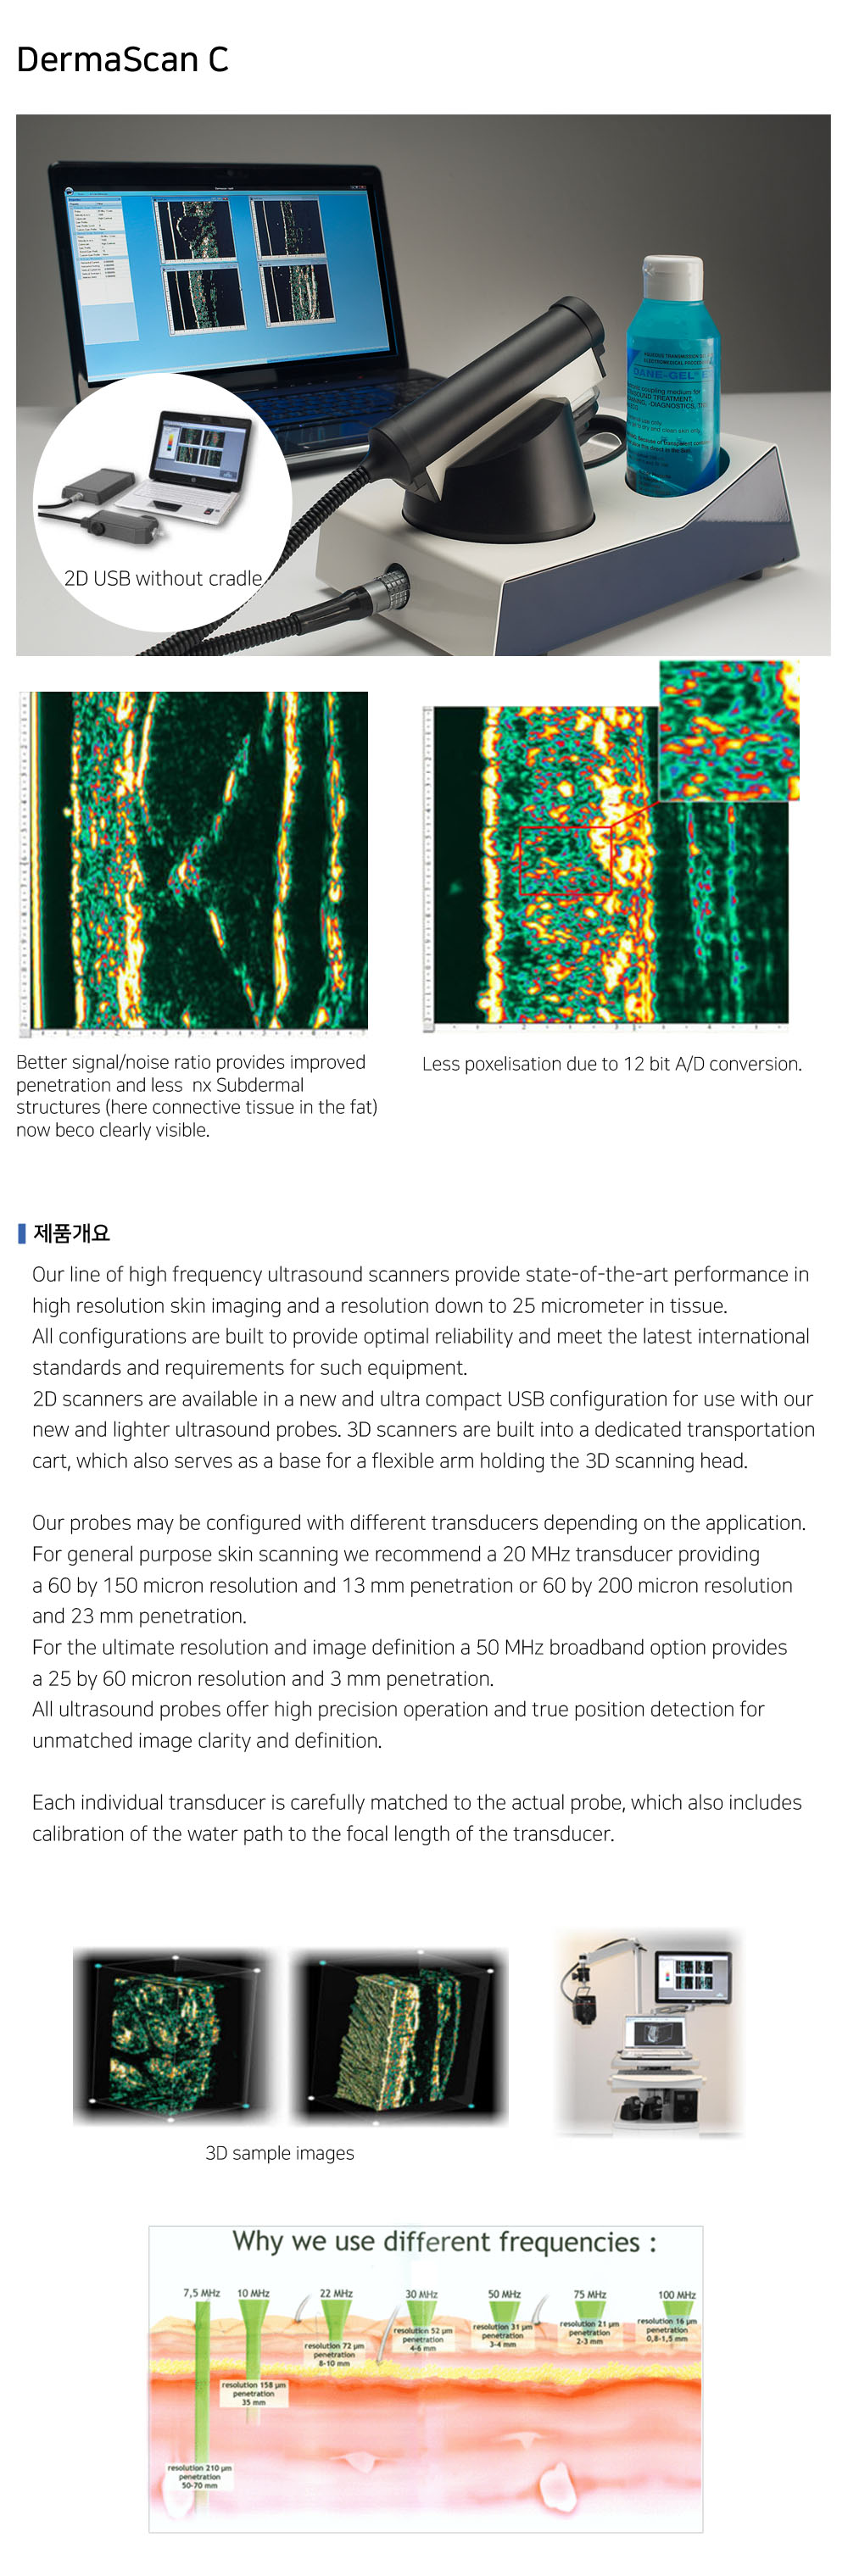

Products

제품소개

20 MHz 2D images